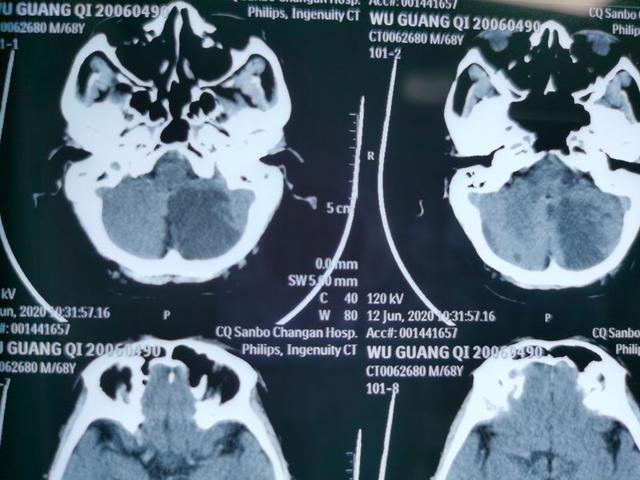

入院后急诊头颅CT

提示左侧小脑半球大片状低密度影;诊断急性脑梗死!!!